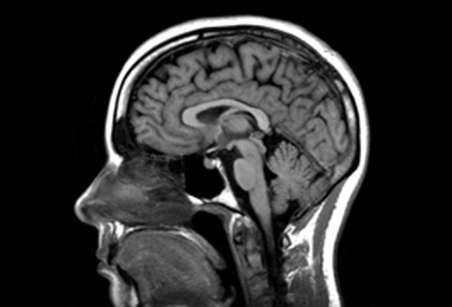

뇌 노화가 형태 변화나 영역 간 공간 배치로 특정 부위의 병리적 취약성을 높일 수 있다는 연구 결과가 발표됐다. 나이가 들면서 뇌 구조가 체계적으로 변하는데, 이러한 변화 패턴이 인지 장애 발생에 영향을 줄 수 있다는 주장이다.

인간의 뇌는 생애 전반에 걸쳐 뚜렷한 구조적 변화를 겪는다. 기존 연구에 따르면, 뇌 용적은 발달기 성장과 성인기 안정화를 거쳐, 노년에 들어서면서 감소하는 ‘역(逆) U자형 궤적’을 보인다. 청년기와 성인 초기 단계까지는 비교적 일정하게 유지되지만, 노년기에는 신경 퇴행으로 위축이 두드러진다.

50세 이전에는 해부학적 변화가 눈에 띄게 드러나지 않지만, 중년을 넘어서면 구조적 변형이 가속화된다. 또한 회백질과 백질이 모두 전반적인 감소세를 보이며, 특히 전두·두정·측두엽 등 특정 영역에서 심한 위축이 나타난다.

미국 캘리포니아대 어바인캠퍼스(UC Irvine)와 스페인 라 라구나대(La Laguna) 공동연구팀은 미국과 영국에 거주하는 30~97세 2,603명의 뇌 MRI 자료를 활용해 연구를 진행했다. 이번 연구는 대뇌 피질 표면의 400개 지점을 기준으로 전후·상하 방향의 전역적 거리와 좌우 반구 39개 피질 및 피하 구조 간 거리를 산출하고, 이를 통해 기하학적 변화를 수치화했다.

지금까지 선행 연구들이 주로 뇌 부피 축소나 피질 두께 감소에 초점을 맞췄다면, 이 연구는 뇌 전체의 공간적 기하 구조와 좌우 반구 간 대응 영역의 거리 변화를 정량적으로 분석했다는 점에서 차별화된다.